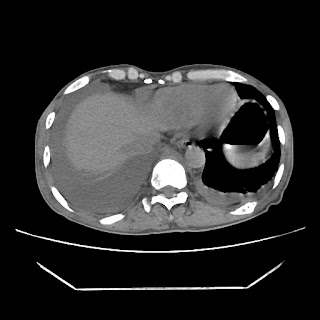

A 56 years old man with

HRCT done on summer season starting 2016